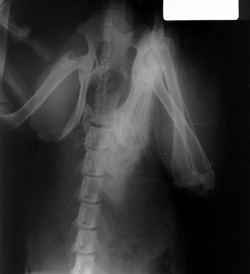

Hands In the Primary Beam